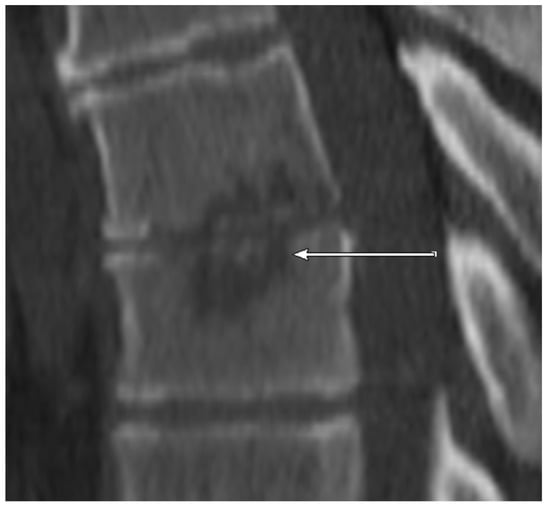

CT: NSE (Figure 4, sclerotic erosion for better differentiation in Figure 5) was observed in 6/11 (54.5%) patients with positive microbiology but only in 1/29 (3.4%) samples with negative microbiology.

Figure 4. CT scan (sagittal reconstruction) of thoracic spine level Th6-Th7 showing non-sclerotic erosions of adjacent endplates of the thoracic spine in 55-year old patient. The detected pathogen after CT-guided biopsy was E. coli.

Figure 5. CT scan (sagittal reconstruction) of lumbar spine level L2-L3. As opposed to Figure 4 showing marginally sclerotic erosions of adjacent endplates of the lumbar spine in 77-year old patient. No detected pathogen after CT-guided biopsy.